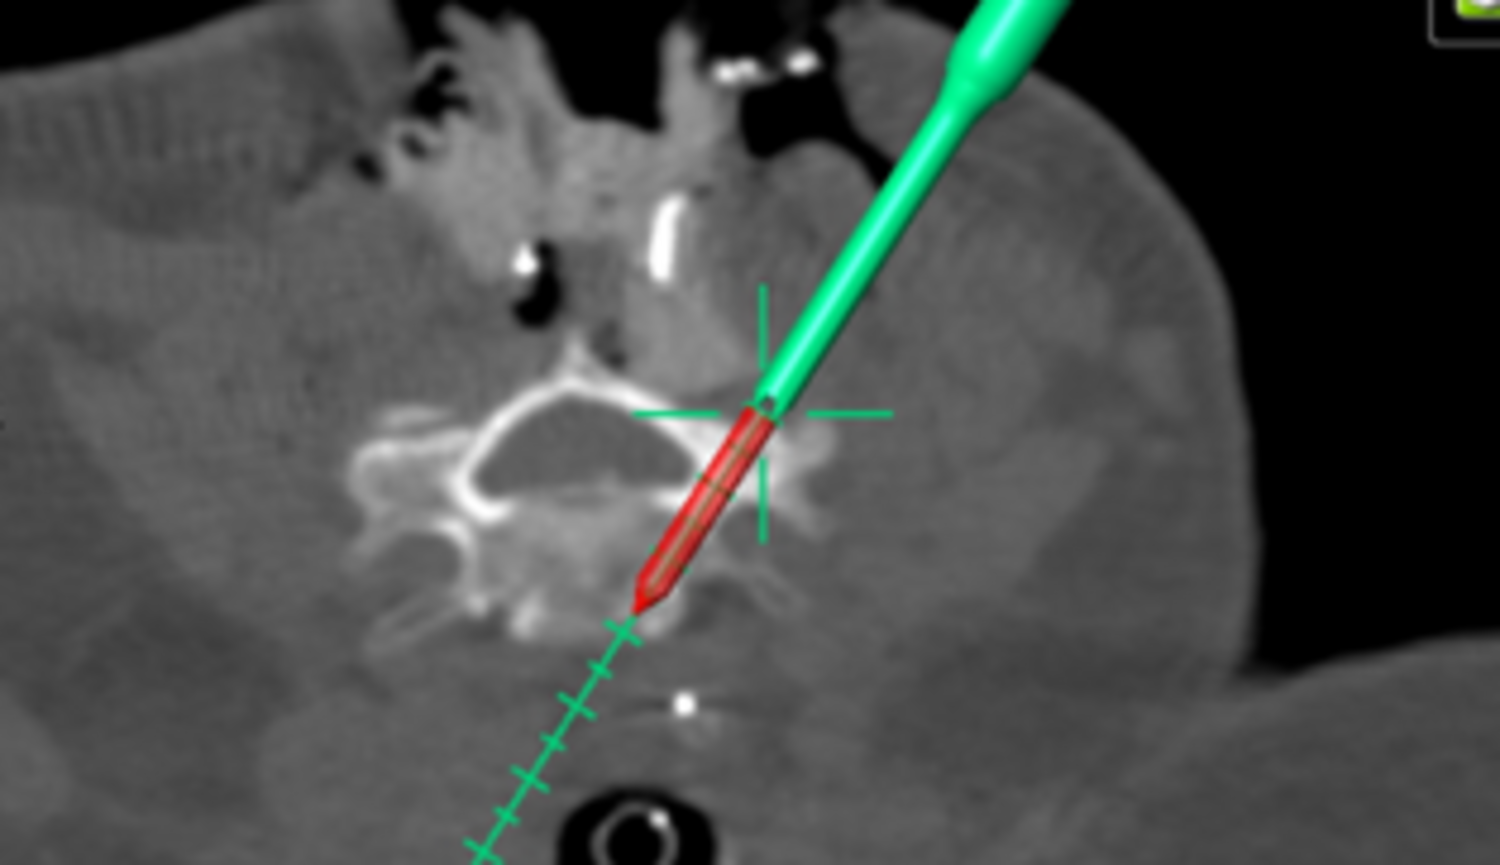

Seit 2017 führen wir unsere Stabilisierungs- und Versteifungsoperationen mit einem intraoperativen CT (s.o. AIRO©, Fa. Brainlab) durch. Diese intraoperative Computertomographie liefert direkt im Operationssaal während des Eingriffs hochauflösende Bilder von der Wirbelsäule. Zusammen mit einer Navigationssoftware wird ein dreidimensionaler Plan der entsprechenden Körperregion erzeugt. Mit Hilfe der Bildgebung können wir die notwendigen OP-Schritte plangerecht umsetzen und z.B. Implantate mit sehr hoher Präzision einsetzen. Gerade bei komplizierten Eingriffen an der Wirbelsäule hilft die neue OP-Technik, Patienten sicher und schonend zu therapieren. Die intraoperative Bildgebung, direkt im OP, erlaubt komplexe Operationen genauer und sicherer durchzuführen und dem Operateur noch während der Operation das Ergebnis zu überprüfen und bei Bedarf zu optimieren. Belastende Folgeoperationen sind so deutlich seltener und die Behandlungsqualität und Sicherheit für Patienten dadurch erheblich verbessert.